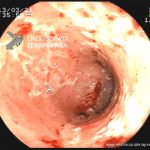

- Doença de Crohn em atividade